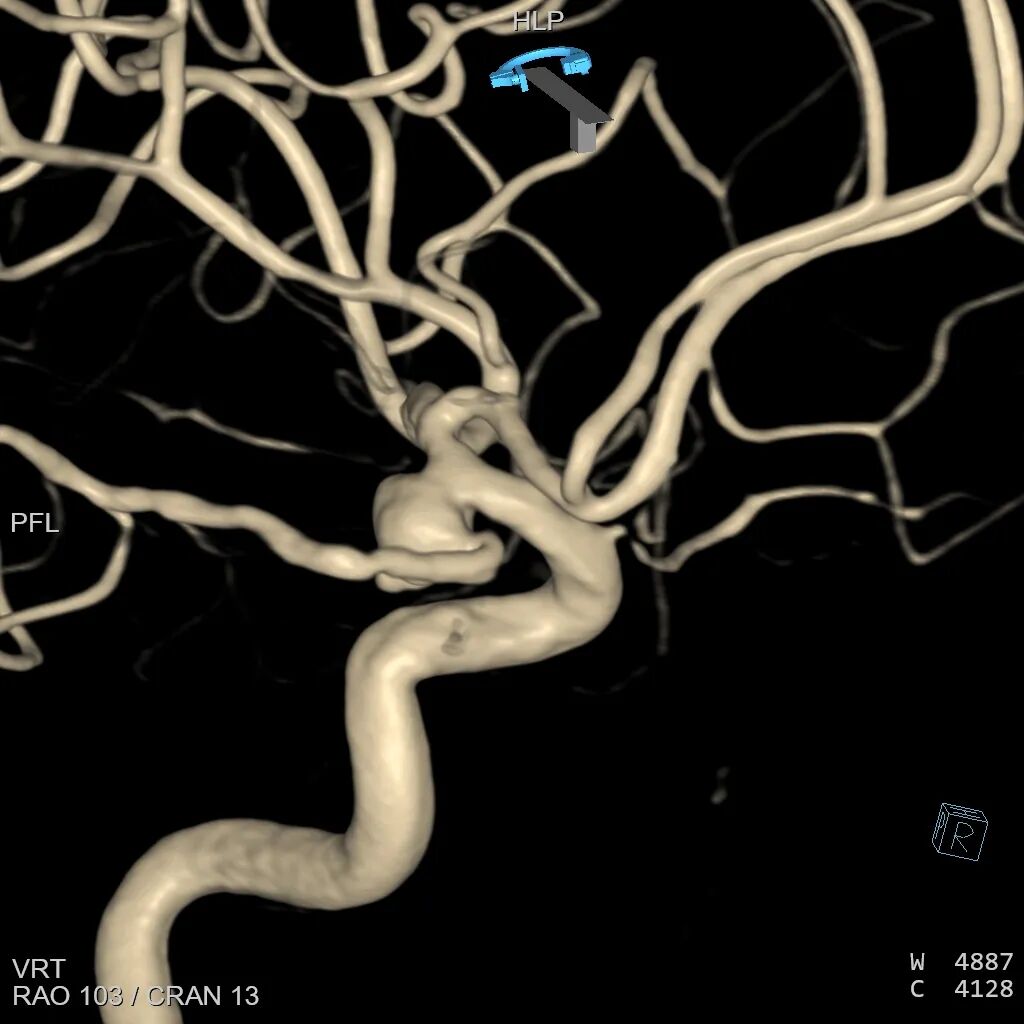

左侧颈内动脉3D造影可见动脉瘤位于后交通动脉起始处。

3D血管造影可见左侧后交通动脉瘤,大小约7.05×7.47mm,瘤颈3.68mm,考虑胚胎型大脑后动脉。

3D血管造影,选择合适的工作角度:分析载瘤动脉与动脉瘤之间的关系,动脉瘤完全由后交通动脉发出,且后交通动脉从颈内动脉处折返发出,微导丝超选进入后交通动脉角度刁钻,再次向患者家属交代病情,建议开颅夹闭,患者家属理解介入手术困难,仍要求介入治疗。